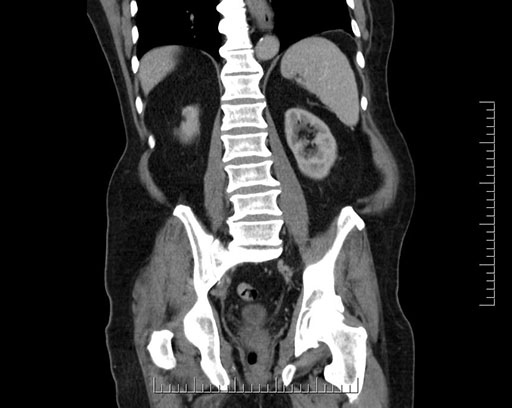

Imaging Analysis

Look through the patient's CT scan to identify any areas of concern for the necessary procedure.

Based on your CT findings, which issue(s) would give reason for "planned slowing down moment(s)" in this case?